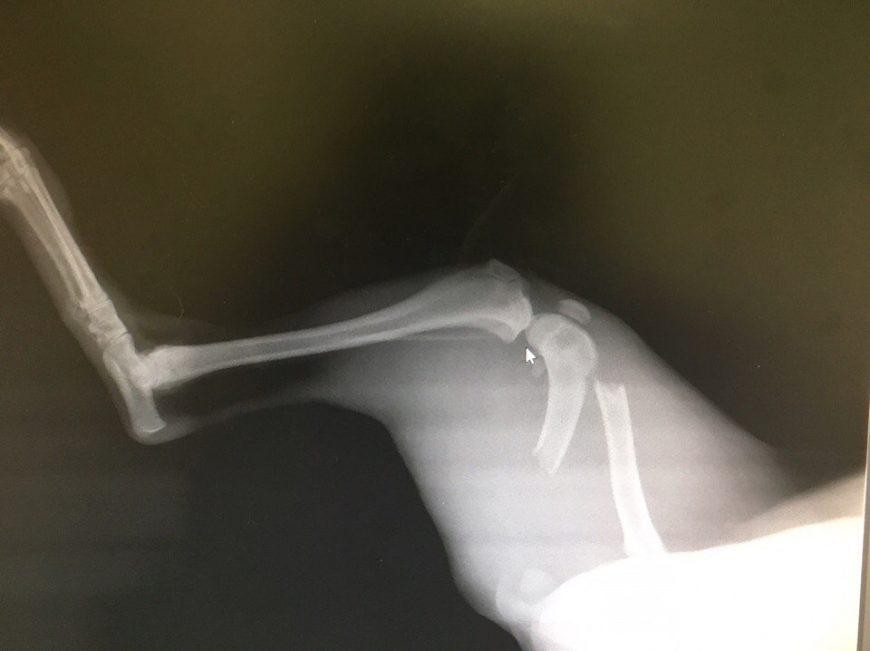

Перелом

Перелом – это нарушение целостности кости. Он сопровождается повреждением окружающих тканей. Возникают в результате травм.Чаще всего кошки ломают конечности, челюсти, ребра, хвост и таз. Закрытый перелом – кожные покровы в месте перелома не поврежденыОткрытый перелом – когда в месте перелома есть рана, из которой может быть видна кость.

Симптомы:Не могут шевелить травмированной частью телаНе могут опираться на травмированную частьБольОтекНеестественное положение части телаКровотечениеПри переломе ребер – сложно дышатПри переломе челюсти - слюнотечение

Первая помощь:Если перелом открытый – постарайтесь остановить кровь с помощью полотенца или марли. Обездвижьте травмированную часть тела.Отвезите к ветеринару.Лечение:Проводят операцию. Устанавливают специальные спицы в кости. Постепенно кости срастаются.